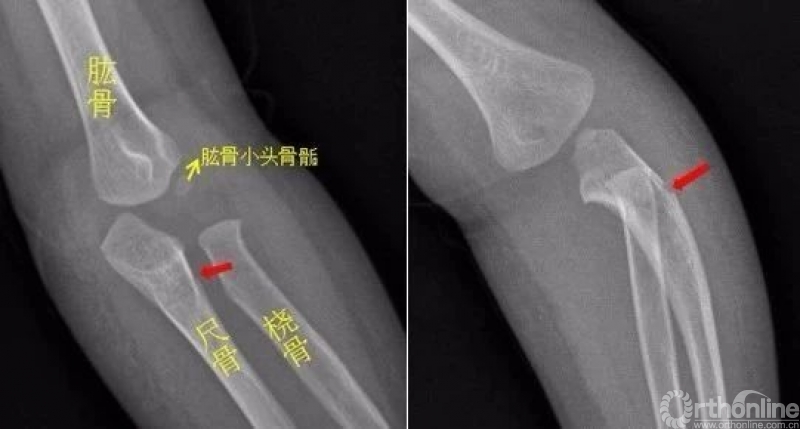

肘关节

左侧尺骨上段见骨折透亮线,断端稍移位成角。左侧尺骨上段青枝骨折

右肘关节内侧见游离骨碎片影,侧位示骨碎片位于右肘关节背侧,右尺骨近端背侧骨质部分缺如。右尺骨近端背侧撕脱性骨折。